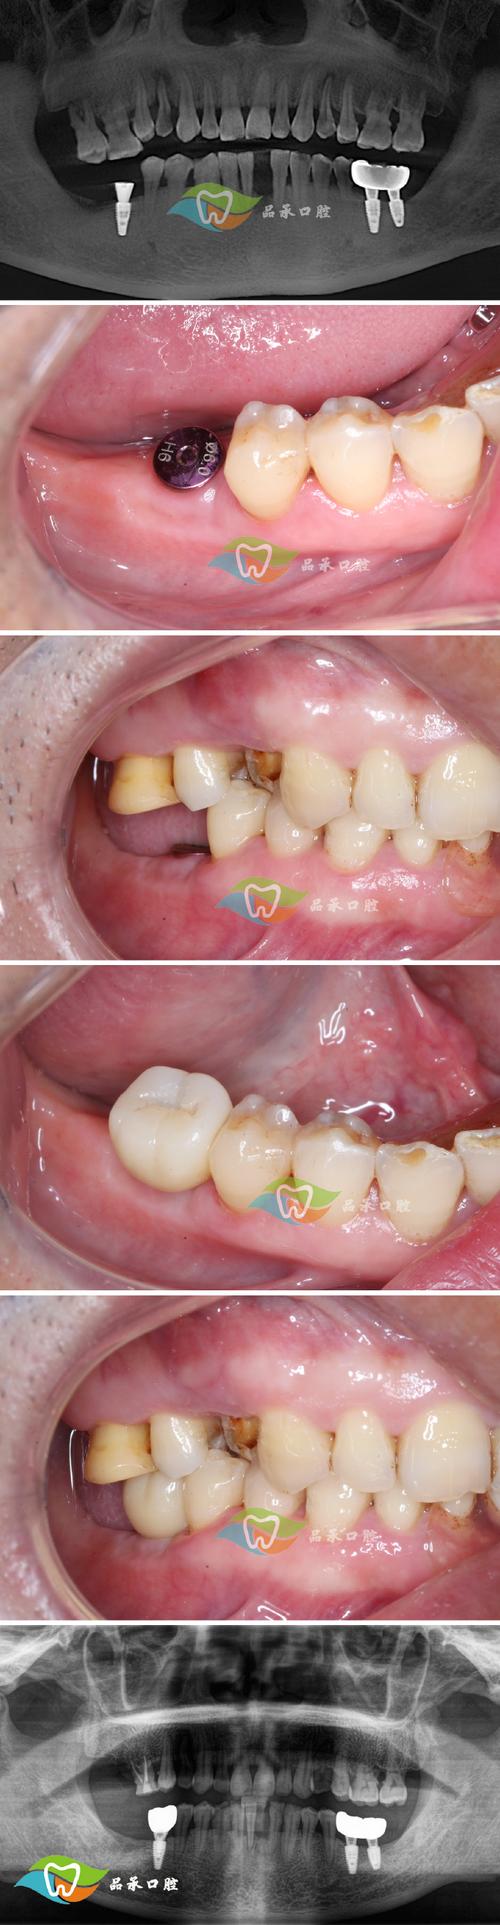

(图片来源网络,侵删)- 感染: 失败常伴随感染(如种植体周围炎),可能导致局部肿胀、疼痛、流脓,甚至发展为更严重的骨髓炎或全身感染。

(图片来源网络,侵删)